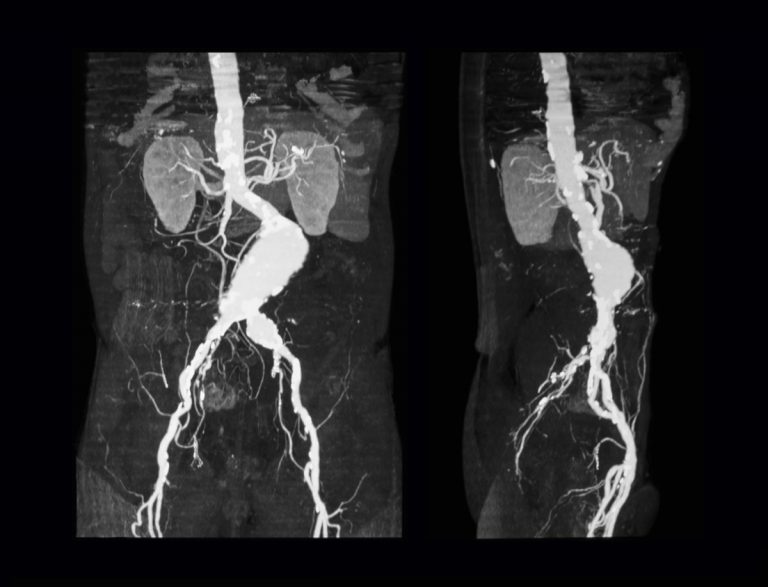

Un aneurisma aórtico abdominal es un agrandamiento de la parte baja de la aorta que se extiende a.

aneurisma de la aorta abdominal La aorta va desde el corazón hasta el. Recibe sangre con gran contenido en oxígeno. Cirugía vascularrupturas de aneurisma de la aorta abdominal: La cirugía de reparación abierta de aneurisma aórtico abdominal (aaa) se realiza para arreglar una parte dilatada de la aorta. Si tienes un aneurisma de la aorta abdominal en expansión, podrías notar lo siguiente: La incidencia de aaai en. En este artículo examen físico pruebas de detección y de diagnóstico ¿quiénes deben someterse a un examen de detección de aneurisma de aorta torácica? Los aneurismas aórticos aneurismas aórticos la aorta, que mide alrededor de 2,5 cm de calibre o diámetro, es la arteria más grande del cuerpo.

Aneurisma de la aorta abdominal en un lactante Cirugía Cardiovascular

Source: www.elsevier.es